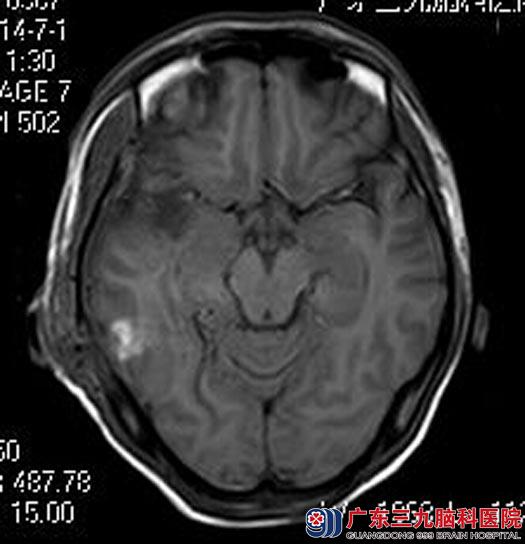

完善相关检查后,由鲁明主任主刀,在全麻下行右侧颞叶内侧脑室三角区海绵状血管瘤切除+前颞叶致痫灶切除术,术中导航定位,显微镜下见暗红色病变组织,质韧、边界欠清,血供丰富,周围黄色含铁血黄素沉着,逐步分离,全切病变。术后,阿华再也没有出现过失神发作,术后病理结果:海绵状血管瘤。

手术后